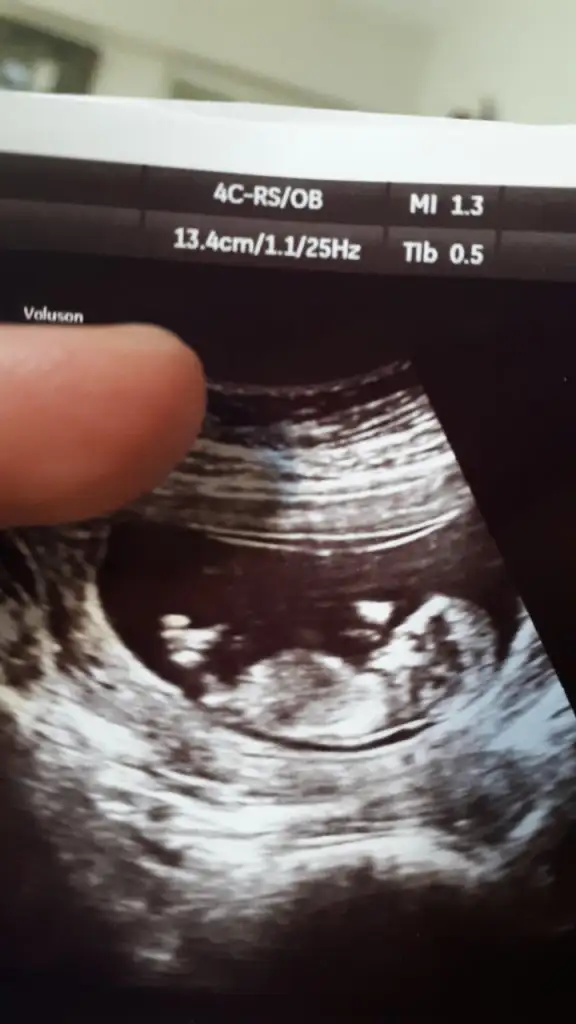

dr soylemeden siz gorun genital nub teorisi ( bebegin cinsiyeti)

Bizde tahmin alabilir miyiz 13+2

• IMG_20190807_164547.webp

IMG_20190807_164547.webp

19,9 KB · Görüntüleme: 75